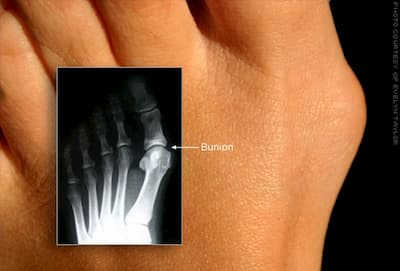

Fallen archesLigaments connect bone to bone or joints where tendons connect bone to muscles.  If the ligaments are not able to support the joints, this leads to collapsing of the arches or pronation.  Pronation is the action of the arches falling and collapsing and the result is flat feet.   Approximately 95% of people with Down syndrome have flat feet.    Flat feet results in problems such as bunions, ankle instability and knee and hip subluxation.

It is recommended to start at an early age wearing supportive shoes and insoles. Higher topped shoes with the most support are recommended. Due to flat feet, only insoles that have a 3 point correction in the heel, arch and forefoot will actually keep the foot from pronating.bunions